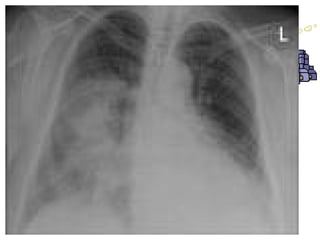

2. Chest x-ray

• Distribution oflung involvement in bronchial and lobar pneumonia. • In bronchopneumonia (left), patchy areas of consolidation occur. • In lobar pneumonia (right), an entire lobe is consolidated

DX finding &assessment 1. History, physical examination. 2. Chest x-ray 3. Blood culture (bacteremia) 4. Sputum examination. 5. Bronchoscopy is often used with pt. with acute sever infection or immuno-compromized pt.